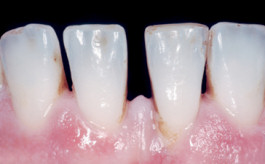

Parodontitis wird durch Bakterien verursacht, die sich zwischen Zahn und Zahnfleisch ansammeln. Werden diese Bakterien nicht entfernt, bilden sich mit der Zeit harte Belaege auf den Zähnen und in den Zahnzwischenräumen. Es kommt zu Entzündungen, Rötungen, Schwellungen und einer erhöhten Blutungsneigung des Zahnfleisches.

In der Folge können die Fasern, die die Zähne mit dem Kieferknochen verbinden, geschädigt werden. Das Zahnfleisch löst sich vom Zahn, Zahnfleischtaschen entstehen und weitere Bakterien können sich dort ansammeln. Wird die Parodontitis nicht behandelt, kommt es zum Knochenabbau und die Zähne beginnen sich zu lockern.

Die Praxis bietet spezielle Lösungen an, um das Fortschreiten dieser Erkrankung zu bremsen. Nach einer Parodontitisbehandlung ist es unverzichtbar, die Zähne in individuell empfohlenen Abständen professionell reinigen zu lassen. Je nach Schweregrad und persönlichem Risiko, etwa bei Diabetes oder Rauchen, sind drei bis vier professionelle Reinigungen pro Jahr sinnvoll.

Diagnose

Zunächst wird die Art und Schwere der Parodontitis bestimmt. Mit einem Sondierungsgerät werden die Tiefe der Zahnfleischtaschen und der Zahnfleischrückgang gemessen. Die Untersuchung ist in der Regel kurz und schmerzfrei. Bei Bedarf zeigen Röntgenaufnahmen den Zustand des Kieferknochens.